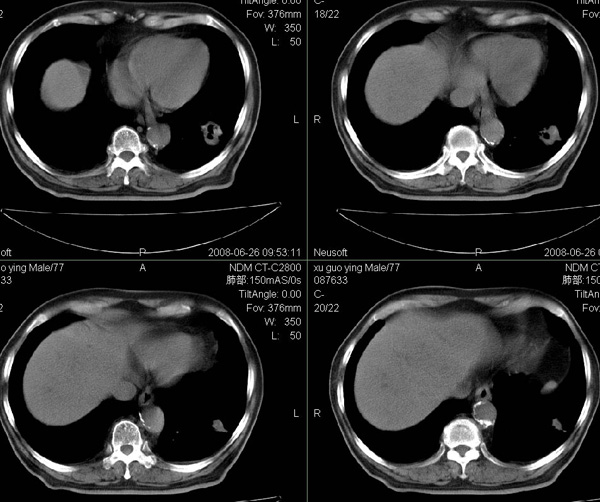

以下是引用狙击手在2008-6-26 20:16:00的发言:[br]上腹部除了胆囊大一点,其余未见明显异常,肺尖部见纤维条索样影,左肺下叶见空洞样占位,壁较厚,临近胸膜见牵拉,周围未见卫星灶,考虑:1:左下肺周围性肺癌;2:肺尖部陈旧性结合灶。

以下是引用liuqiang在2008-6-26 21:11:00的发言:[br]上腹部除了胆囊大一点,其余未见明显异常,肺尖部见纤维条索样影,左肺下叶见空洞样占位,壁较厚,临近胸膜见牵拉,周围未见卫星灶,考虑:1:左下肺周围性肺癌;2:肺尖部陈旧性j结核灶。